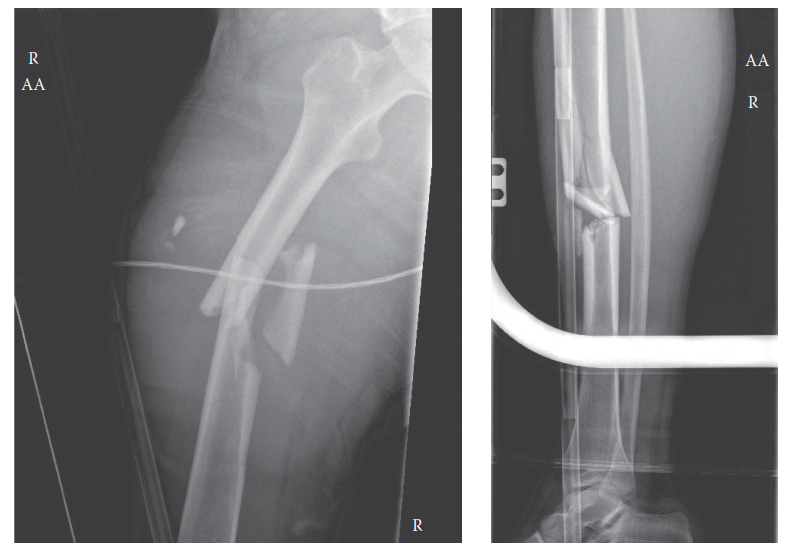

A 25yearold man has been involved in a highspeed road traffic accident. What do these radiographs show and ho…

Can you describe the radiographs and tell me what your immediate concerns would be? These are AP and lateral …